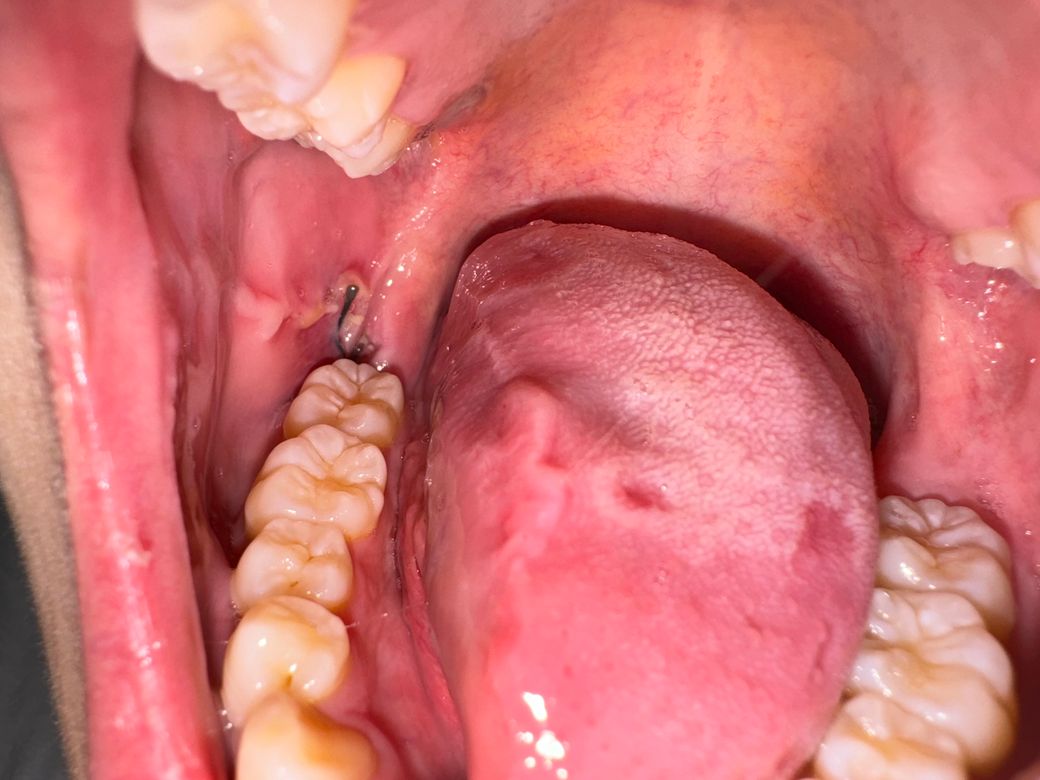

저기 하얀 부분이 가만히 둬도 욱씬거리고 입 크게 벌리면 너무 아파요ㅠㅠ 사랑니 발치는 오늘로 5일째인데 입에서 짠맛도 계속나고 악취도 좀 나는것 같아요.. 인후통도 아직 있고요ㅠ 정상인건가요?

사랑니 발치 후 5일이 지났음에도 불구하고 욱씬거리는 통증, 입을 크게 벌릴 때의 고통, 지속적인 짠맛과 악취 발생, 그리고 인후통이 여전히 존재한다면, 이는 회복 과정에서 발생할 수 있는 일반적인 증상들을 넘어서는 것일 수 있습니다. 일반적으로 사랑니 발치 후에는 일정 기간 동안 붓기, 약간의 통증, 그리고 불편함이 발생할 수 있으나, 증상이 개선되기 시작하는 것이 보통입니다.

지속적인 짠맛과 악취, 그리고 통증이 계속된다면, 이는 감염의 가능성을 포함하여 발치 부위의 정상적이지 않은 회복을 나타낼 수 있습니다. 특히, '건조구'라고 불리는 상태가 발생했을 가능성이 있습니다. 건조구는 발치 후 생성되어야 할 혈전(피 덩어리)이 제대로 형성되지 않거나, 일찍 빠져나가 발치한 구멍이 노출되어 공기, 음식, 세균 등에 직접 노출되어 통증과 감염을 유발하는 상태를 말합니다.

인후통은 발치 부위의 감염이 주변 조직으로 퍼질 수 있다는 신호일 수도 있으며, 이는 전반적인 구강 건강 상태와 연관이 있을 수 있습니다. 이러한 증상들은 적절한 치료가 필요한 상태일 수 있으므로, 담당주치의와 상의해보시기 바랍니다.